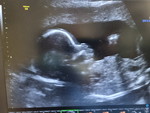

กำลังตั้งครรภ์